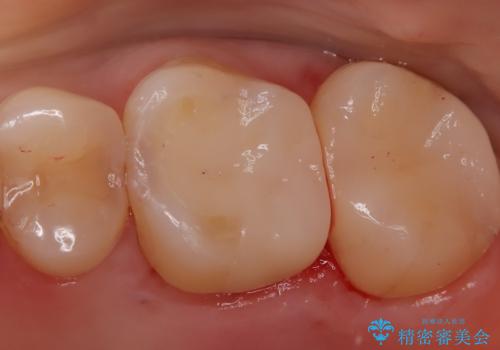

【セラミックインレー】虫歯になった詰め物部分を修復

- 前医で治療された詰め物の部分に、定期検診で虫歯が見つかったため、セラミックインレーにて修復治療を行いました。

接着時にはラバーダム防湿を行っています。